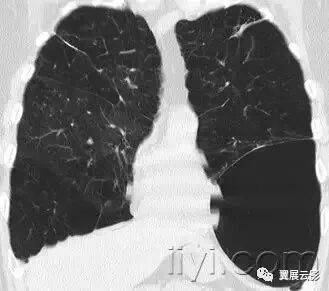

十九、肺实变:

病理学:肺实变是指渗出,或者其他疾病成分替代肺泡内气体,导致肺实变。

平片和CT:肺实变表现为肺实质密度的均匀一致性增高,导致肺血管和气道壁边缘不清。有时可见含气支气管征。只有在极少数的情况下,肺实变的密度变化有助于鉴别诊断,例如脂性肺炎是密度减低,胺碘酮中毒时密度增高。

图示为多灶性的肺实变。